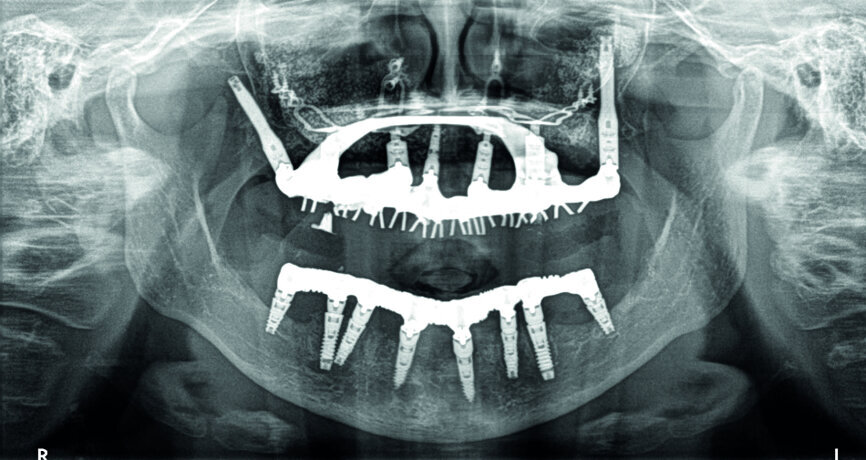

Cas 2d : contrôle radiologique